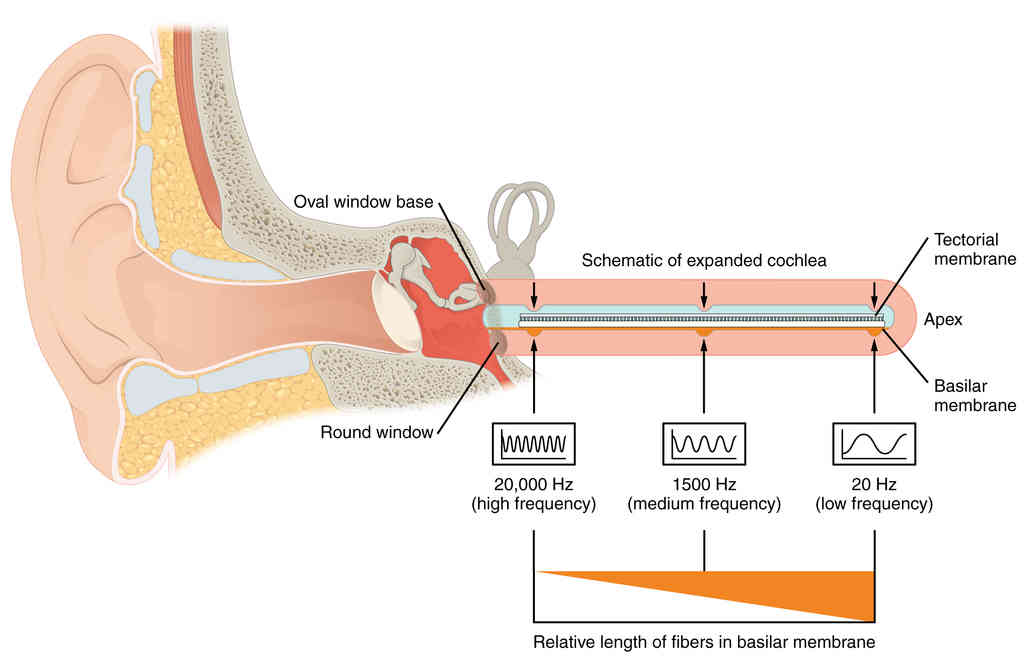

This page is under construction. For now, it is just a resource of the images found in the OpenStax Anatomy and Physiology Handbook. It wil slowly change into a revision tool. Each slide has a number. Use this to refer to the slide. When completed, it will have an unlabelled section, with labelled slides in parallel. On the unlabelled slides, write your answer and use the labelled slide to assess yourself. Keep track by also noting the number on each slide. Improvement at each attempt is important, more so than full marks on a first attempt.